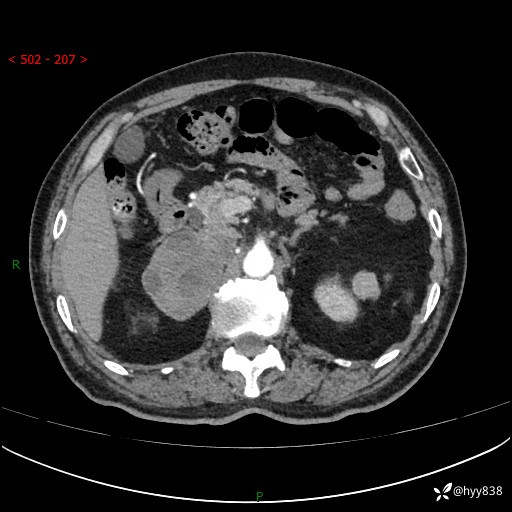

【患者信息】:76岁/男

【主诉】:检查发现右侧肾上腺占位6天

【现病史及既往史】:患者6天前体检发现右侧肾上腺占位,无腰痛,无放射痛,无尿频、尿急、尿痛及肉眼血尿,无畏寒、发热,无恶心、呕吐,今为求进一步治疗,遂来我院就诊,门诊拟“右侧肾上腺占位”收住入院。 起病以来,患者精神、饮食、睡眠可,大小便如常,体力体重无明显变化。

【检查】:肾上腺CT平扫+增强